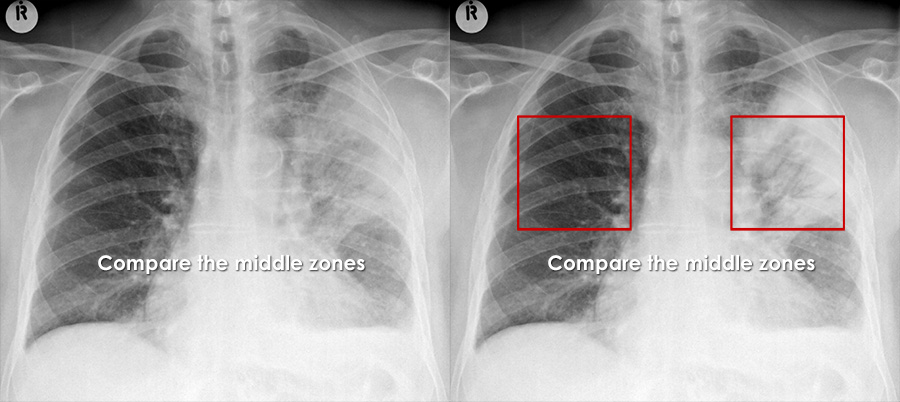

Heart Failure

Feature Description

Cardiomegaly Enlarged cardiac silhouette (CTR > 0.5 on PA film).

Kerley B lines Short, horizontal lines at lung bases representing interstitial oedema.

Upper lobe diversion Prominent upper lobe vessels indicating pulmonary venous hypertension.

Peribronchial cuffing Thickened bronchial walls due to interstitial fluid.

Typical features of CCF on chest X-ray

Typical congestive cardiac failure CXR